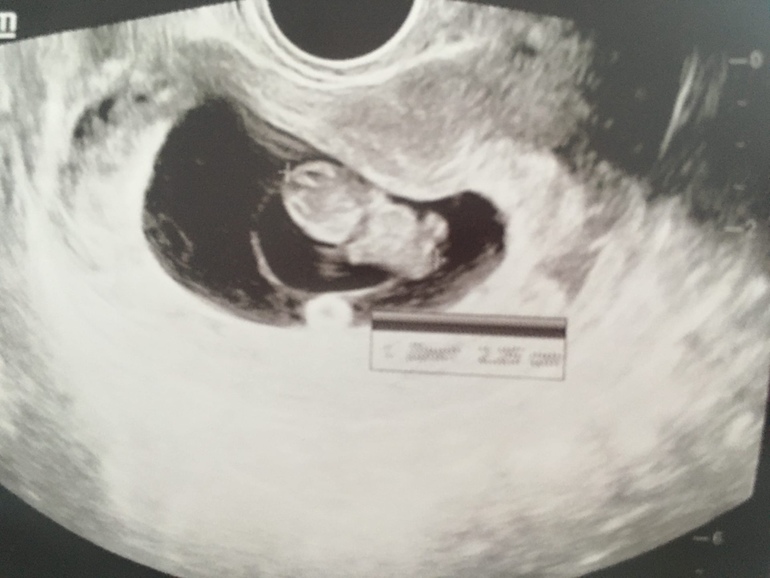

Выпускной у репродуктолога 😊 8+3

Всё о нашей беременностиБыла сегодня на последнем приеме у своего репродуктолога (8 недель 3 дня по месячным). Все хорошо, слава богу никаких отслоек и гематом нет, все соответствует сроку. Человек уже не креветка, а прям... человек!) Хотя врач шутливо назвал "матрешкой"

Так все подробно на узи показал, и позвоночник, и зачатки рук, ног, головной мозг. Лежу и расплываюсь в улыбке, такое тепло внутри, что вот он, мооййй человечек!!!